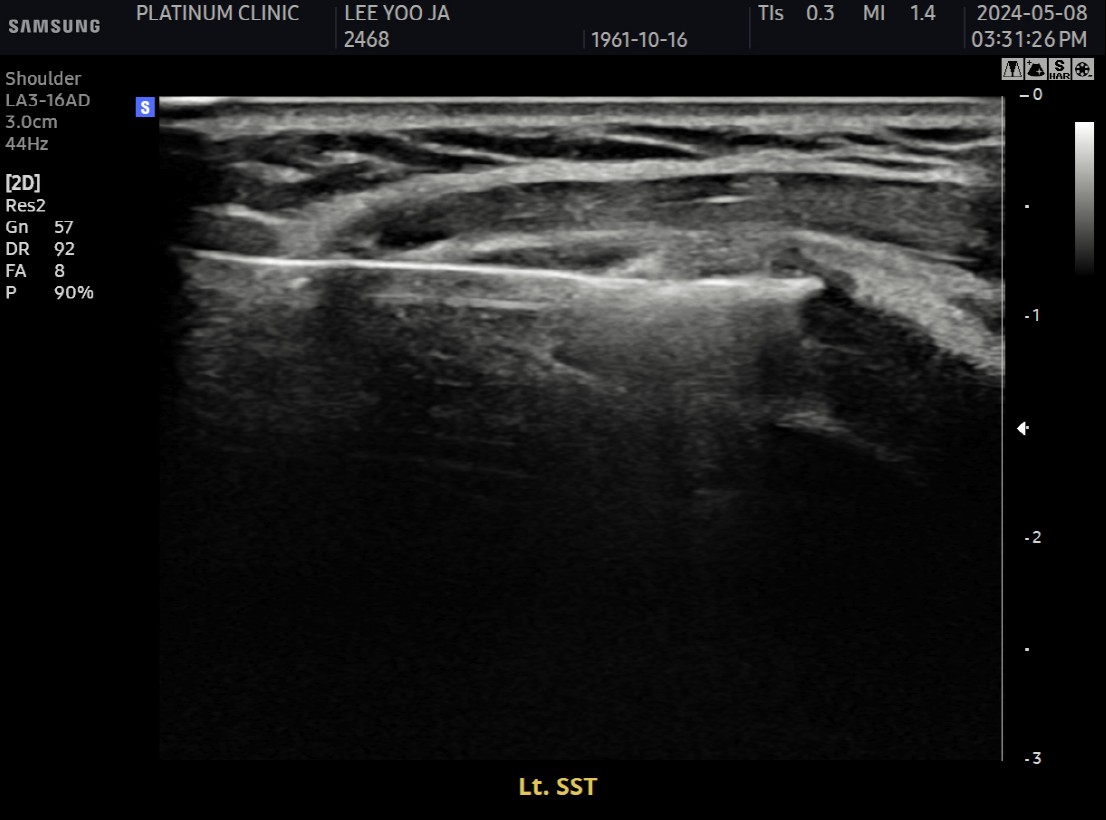

Step 2: 초음파 유도 하 가이드 삽입

초음파로 석회 위치를 실시간 확인하면서 특수 가이드를 삽입합니다.

피부에 작은 절개 (약 2~3mm)

가이드를 석회 바로 옆에 위치

인대를 관통하지 않고 석회에 직접 접근

Step 3: 석회 분쇄

전용 분쇄 기구를 가이드에 통해 삽입하여 석회를 분쇄합니다.

단단한 석회도 물리적으로 깨뜨림

초음파로 분쇄 과정 실시간 확인

석회가 잘게 부서지는 것이 보임